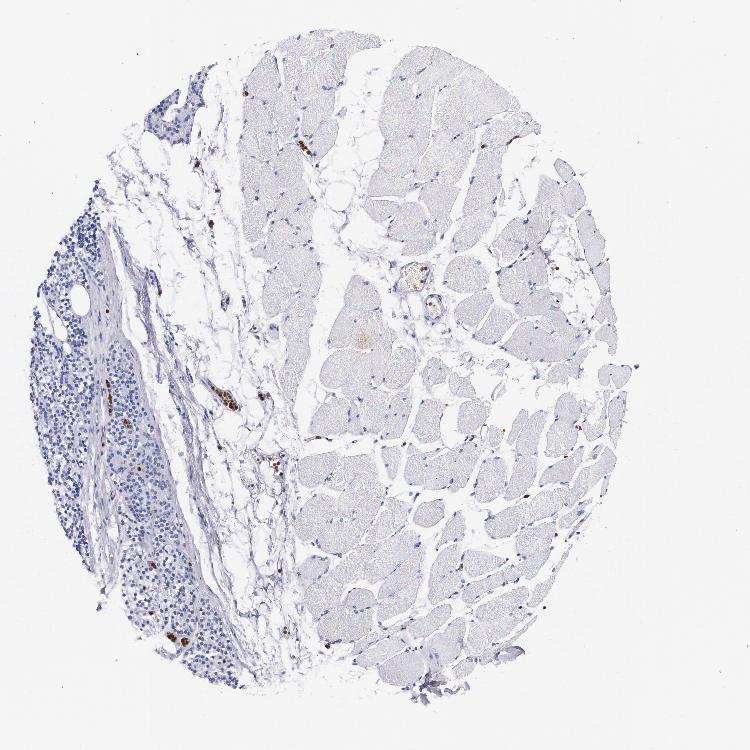

TISSUE PRIMARY DATA SKELETAL MUSCLE Show tissue menu

SKELETAL MUSCLE - Antibody stainingi

Antibody staining in the annotated cell types in the current human tissue is reported as not detected, low, medium, or high, based on conventional immunohistochemistry profiling in selected tissues. This score is based on the combination of the staining intensity and fraction of stained cells.

Each image is clickable and will lead to virtual microscopy that enables deeper exploration of all samples and also displays staining intensity scores, fraction scores and subcellular localization as well as patient and tissue information for each sample.

Antibody HPA024372Antibody CAB002791

Myocytes Not detectedNot detected